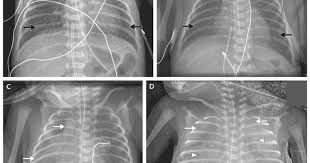

Radiografia toracică a unui caz de irds, cu opacități sindromul de detresă respiratorie acută (ards) are unele asemănări cu irds.

Radiografia toracică a unui caz de irds, cu opacități sindromul de detresă respiratorie acută (ards) are unele asemănări cu irds. Dacă copilul dumneavoastră are dificultăți de respirație sau oricare dintre simptomele de detresa respiratorie și devine brusc apatic, aceasta este o urgență. Detresa respiratorie neonatala prin deficit de surfactant. Detresa respiratorie a nou únascutului. Acum, in aceste zile, în care exista foarte mulți copii cu boli febrile, tuse şi respirație rapidă febra contribuie la creşterea frecvenței cardiace şi a celei respiratorii.